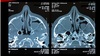

Sinusitis maxiloetmoidal